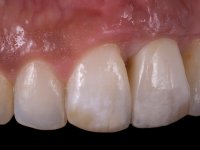

A paciente de sexo feminino de 28 anos de idade perdeu por traumatismo o incisivo central superior esquerdo. Preocupada com o seu sorriso, a paciente apareceu no consultório querendo alinhar os dentes antero-superiores para obter uma aparência mais natural. Sendo fumadora a paciente não apresentava problemas médicos dignos de registo.

A paciente apresenta um desvio da linha média superior de 6 mm para a esquerda. Resultado da ausência do incisivo central superior esquerdo, os dentes adjacentes inclinaram mesialmente para esta zona, limitando o espaço disponível para a reabilitação prostodontica. Existe uma significativa desarmonia dentária negativa no arco maxilar como resultado da ausência do 21, ausência do primeiro pre-molar com um espaço residual, significativa redução coronária do segundo pre-molar direito, migração dos dentes posteriores para os espaços não preenchidos e uma mesialização molar superior esquerda e direita com uma relação molar em Classe II. Ambos os caninos esquerdo e direito mostram uma relação Classe II na posição de inter-cuspidação máxima. A paciente apresenta uma linha de sorriso média, um biótipo gengival médio grosso, apresenta uma correcta higiene oral sem doença periodontal. Não apresenta hábitos para –funcionais. O exame radiográfico mostra uma significativa inclinação dos eixos dos dentes 11 e 22 com espaço entre a porção apical das raízes. A análise cefalométrica foi feita com o intuito de explorar a hipótese de conseguir arranjar espaço para a colocação de um implante e de uma coroa no local do dente 21. Finalmente a morfologia do osso residual presente na região anterior da maxila foi avaliado com uma TAC, revelando uma perda das dimensões da parede óssea vestibular.